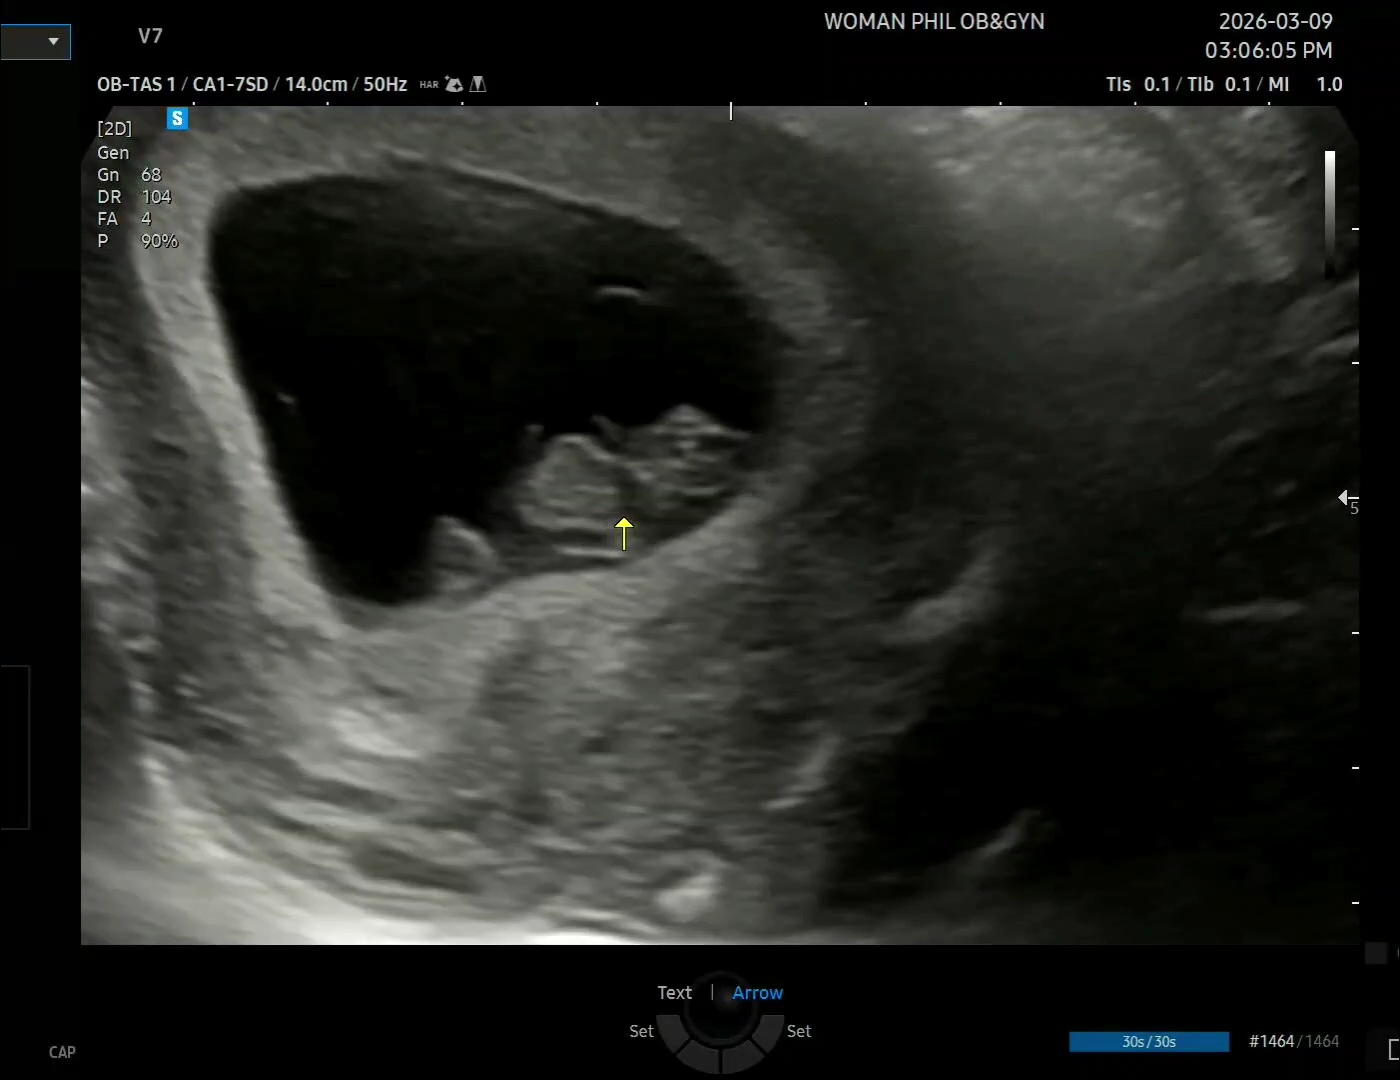

¿À´ÃÀ» ±â´Ù·È´Ù!!

À۳⿡ À¯»êÇß´Ù´Â ±Û ½è´Âµ¥ ±â¾ïÇÏ·Á³ª?

À§·ÎÇØÁÖ´Â »ç¶÷µé Âü ¸¹¾Ò´Âµ¥ ÇѸíÇѸí Á¤¸» °í¸¶¿ü¾î

±×·¡¼­ °í¸¶¿òÀ» º¸´äÇϱâ À§ÇØ »õ·Î ¸¸µé¾î¿Ô´Ù.

¾ÆÁ÷ 8ÁÖÂ÷¶ó 2µî½ÅÀ̾ß.

2cm¿¡ üÁß 4gÁ¤µµ µÈ´Ù´Âµ¥, ¹Ì´Ï ÇÖ¼Ò½º 1Æ÷Á¤µµ µÇ°Ú´Ù.

°â»ç°â»ç ¿À´Ã »ýÀϵµ ÃàÇÏÇØÁà

´Ùµé º¹ ¸¹À̹ްí ÇູÇÑ ÇϷ纸³»!!😘